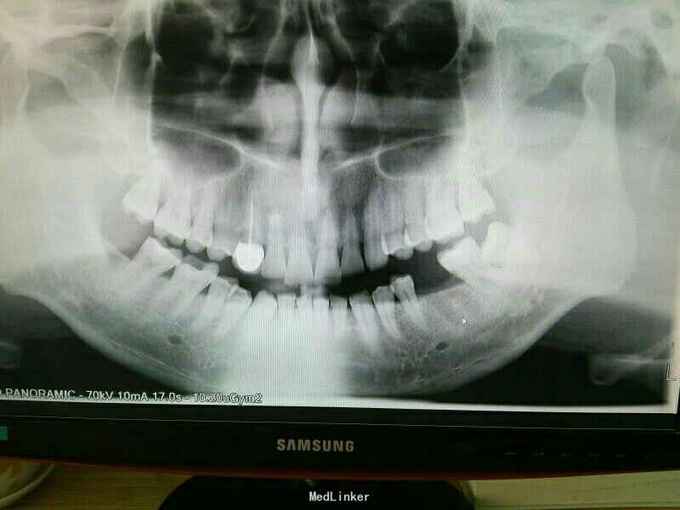

种植牙修复

患者,男,40岁,三月前拔除松动牙,种植修复

左下后牙种植修复